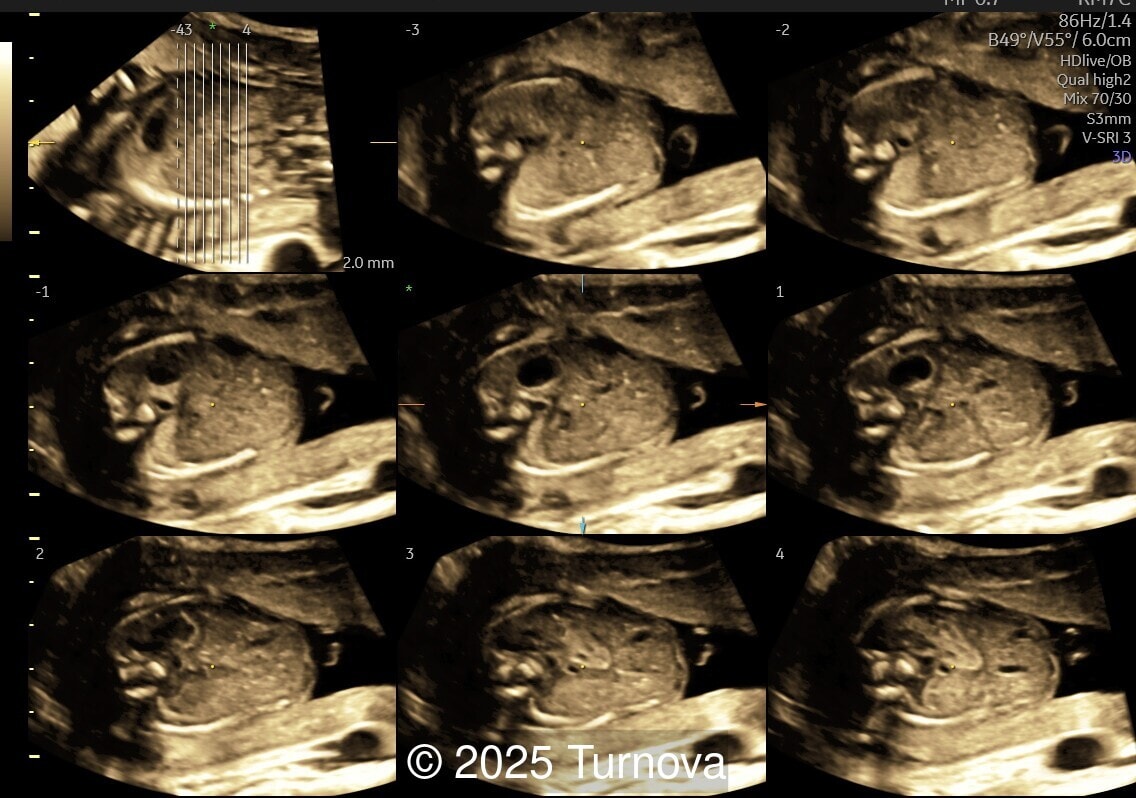

Image 2

A 32-year-old gravida 2, para 1 presented at 19 + 0 weeks of gestation for a routine second-trimester screening ultrasound. Ultrasound examination revealed abnormal subcutaneous tissue and abnormal nuchal fold highly suggestive of trisomy 21. In addition, a marked hepatomegaly was noted, with the liver appearing diffusely hyperechogenic. No ascites or signs of hydrops were present.